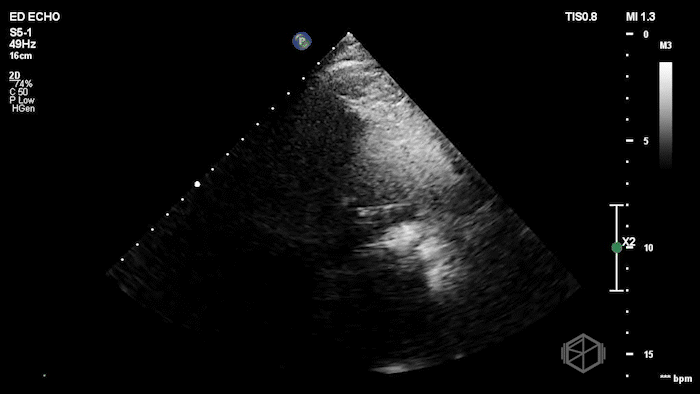

A man with new rapid atrial fibrillation and a man with acute shortness of breath.